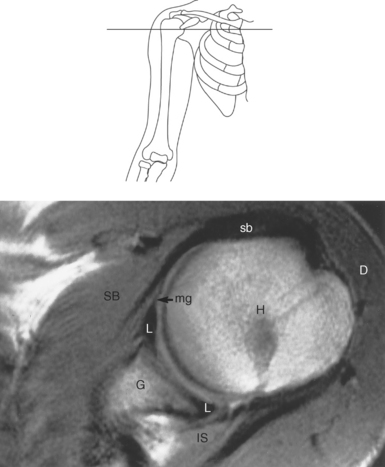

Figure 9.27 Axial, T1-weighted MR scan of shoulder.

Key: c, Clavicle; cc, coracoclavicular ligament; CP, coracoid process; ch, coracohumeral ligament; D, deltoid muscle; H, humeral head; SB, subscapularis muscle; SS, supraspinatus muscle; G, glenoid fossa; L, labrum; ss, supraspinatus tendon; b, tendon of long head of biceps muscle; IG, inferior glenohumeral ligament; mg, middle glenohumeral ligament; sb, subscapularis tendon; T, teres minor muscle.